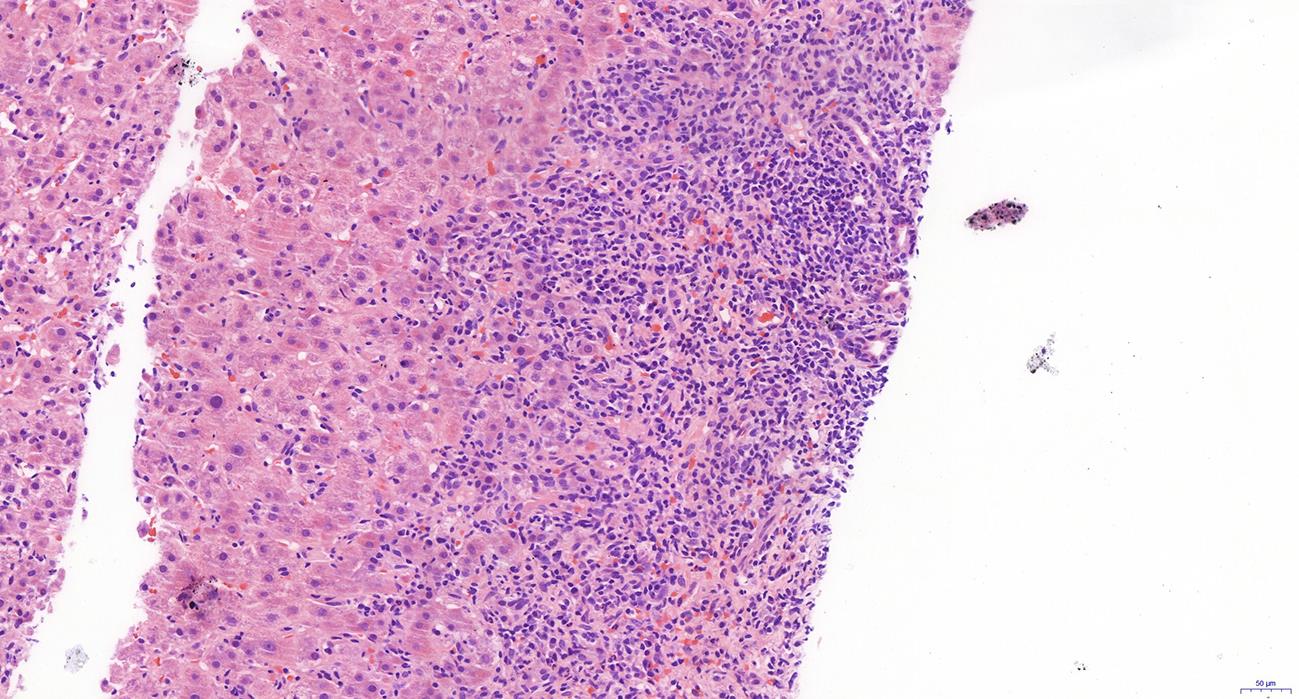

自身免疫性肝炎(AIH)是免疫介导的肝实质炎症性疾病,以高丙种球蛋白血症、自身抗体阳性和典型的肝组织学异常为特征。然而,AIH临床表现多样,缺乏特异性的血清学标志物,因此AIH的诊断困难,具有挑战性。虽然汇管区淋巴浆细胞浸润、界面性肝炎、淋巴细胞穿入现象和肝细胞玫瑰花结为AIH典型的组织学特征,但在AIH中尚可观察到其他的一些形态学改变,包括小叶中心性坏死、Kupffer细胞内透明小球等。所以没有一个单一的组织学特征可直接诊断AIH,需结合临床和实验室检查,并排除其他原因引起的肝脏疾病,方可做出正确的诊断。本文总结了AIH的组织学特征、不同的病理组织学谱、常见的临床问题、主要的鉴别诊断和最新进展。